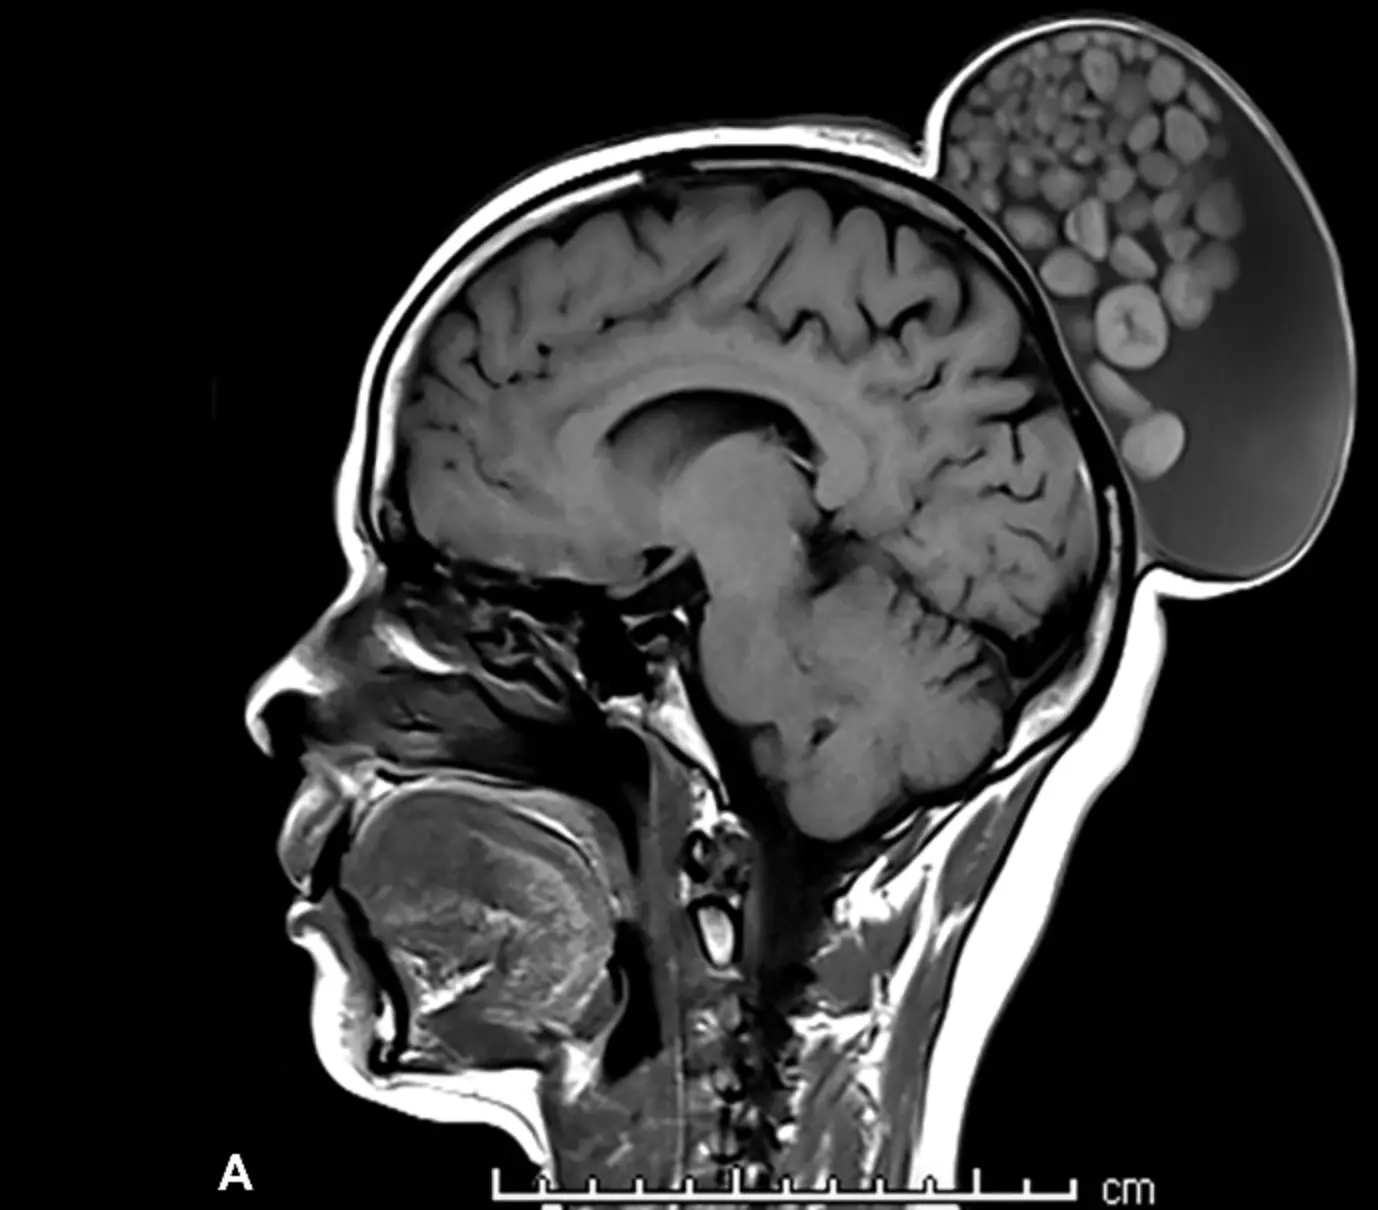

Un kyste ressemblant à "un sac de billes". C’est l’étonnant cas clinique qu’a partagé une équipe de chercheurs indiens de l'Institut des sciences médicales supérieures Sri Sathya Sai dans la revue médicale Radiology, indique le New York Post.

Lorsqu’elle a enfin cherché à obtenir une aide médicale, le kyste avait grossi jusqu’à mesurer plus de 15 cm de long et 10 cm de large. L’équipe médicale a donc décidé d’opérer leur patiente. Lors de son ablation, ils ont remarqué que le kyste était rempli de liquide, de cheveux, de molécules grasses et d’amas de kératine “de tailles variées”.